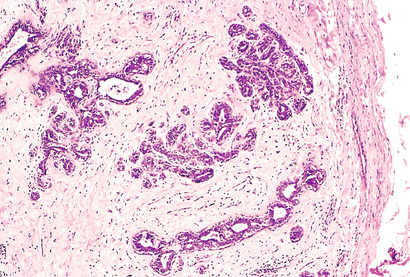

By contrast, while malignant neoplasms exhibit a wide range of parenchymal cell differentiation, most exhibit morphologic alterations that betray their malignant nature. In well-differentiated cancers, these features may be quite subtle (Fig. 6.3). For example, well-differentiated adenocarcinoma of the thyroid gland may contain normal-appearing follicles, its malignant potential being only revealed by invasion into adjacent tissues or metastasis. The stroma carrying the blood supply is crucial to the growth of tumors but does not aid in the separation of benign from malignant ones. The amount of stromal connective tissue does, however, determine the consistency of a neoplasm. Certain cancers induce a dense, abundant fibrous stroma (desmoplasia), making them hard, so-called “scirrhous tumors”.

Next to the development of metastases, invasiveness is the feature that most reliably distinguishes cancers from benign tumors (Figs. 6.9 and 6.10). Cancers lack well-defined capsules. There are instances in which a slowly growing malignant tumor deceptively appears to be encased by the stroma of the surrounding host tissue, but microscopic examination reveals tiny crablike feet penetrating the margin and infiltrating adjacent structures. This infiltrative mode of growth makes it necessary to remove a wide margin of surrounding normal tissue when surgical excision of a malignant tumor is attempted. Surgical pathologists carefully examine the margins of resected tumors to ensure that they are devoid of cancer cells (clean margins).